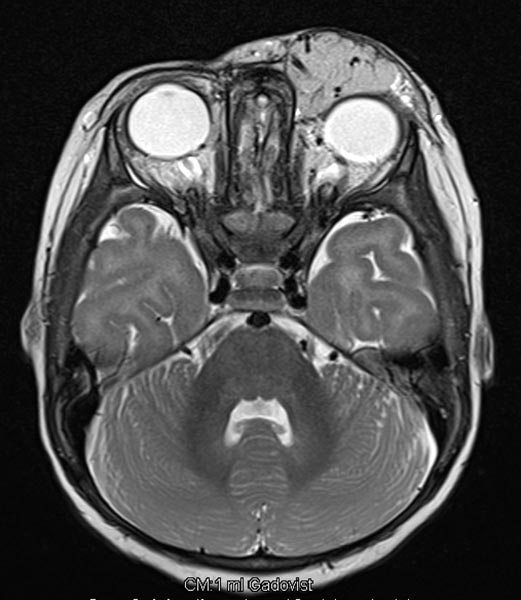

T2-weighted axial MRI with fat saturation. The mass medial to the left eye is relatively homogeneously hyperintense and sharply demarcated from the surrounding tissue. As a sign of strong arterial perfusion, some black, signal-free arterial vessels are seen in the lesion (“flow voids”). This is also typical of an infantile hemangioma.

T2-weighted axial MRI without fat saturation. The mass medial to the left eye is also relatively homogeneously hyperintense in this sequence and shows central flow voids. However, due to the lack of fat saturation, the mass is not as well demarcated from the surrounding adipose tissue.